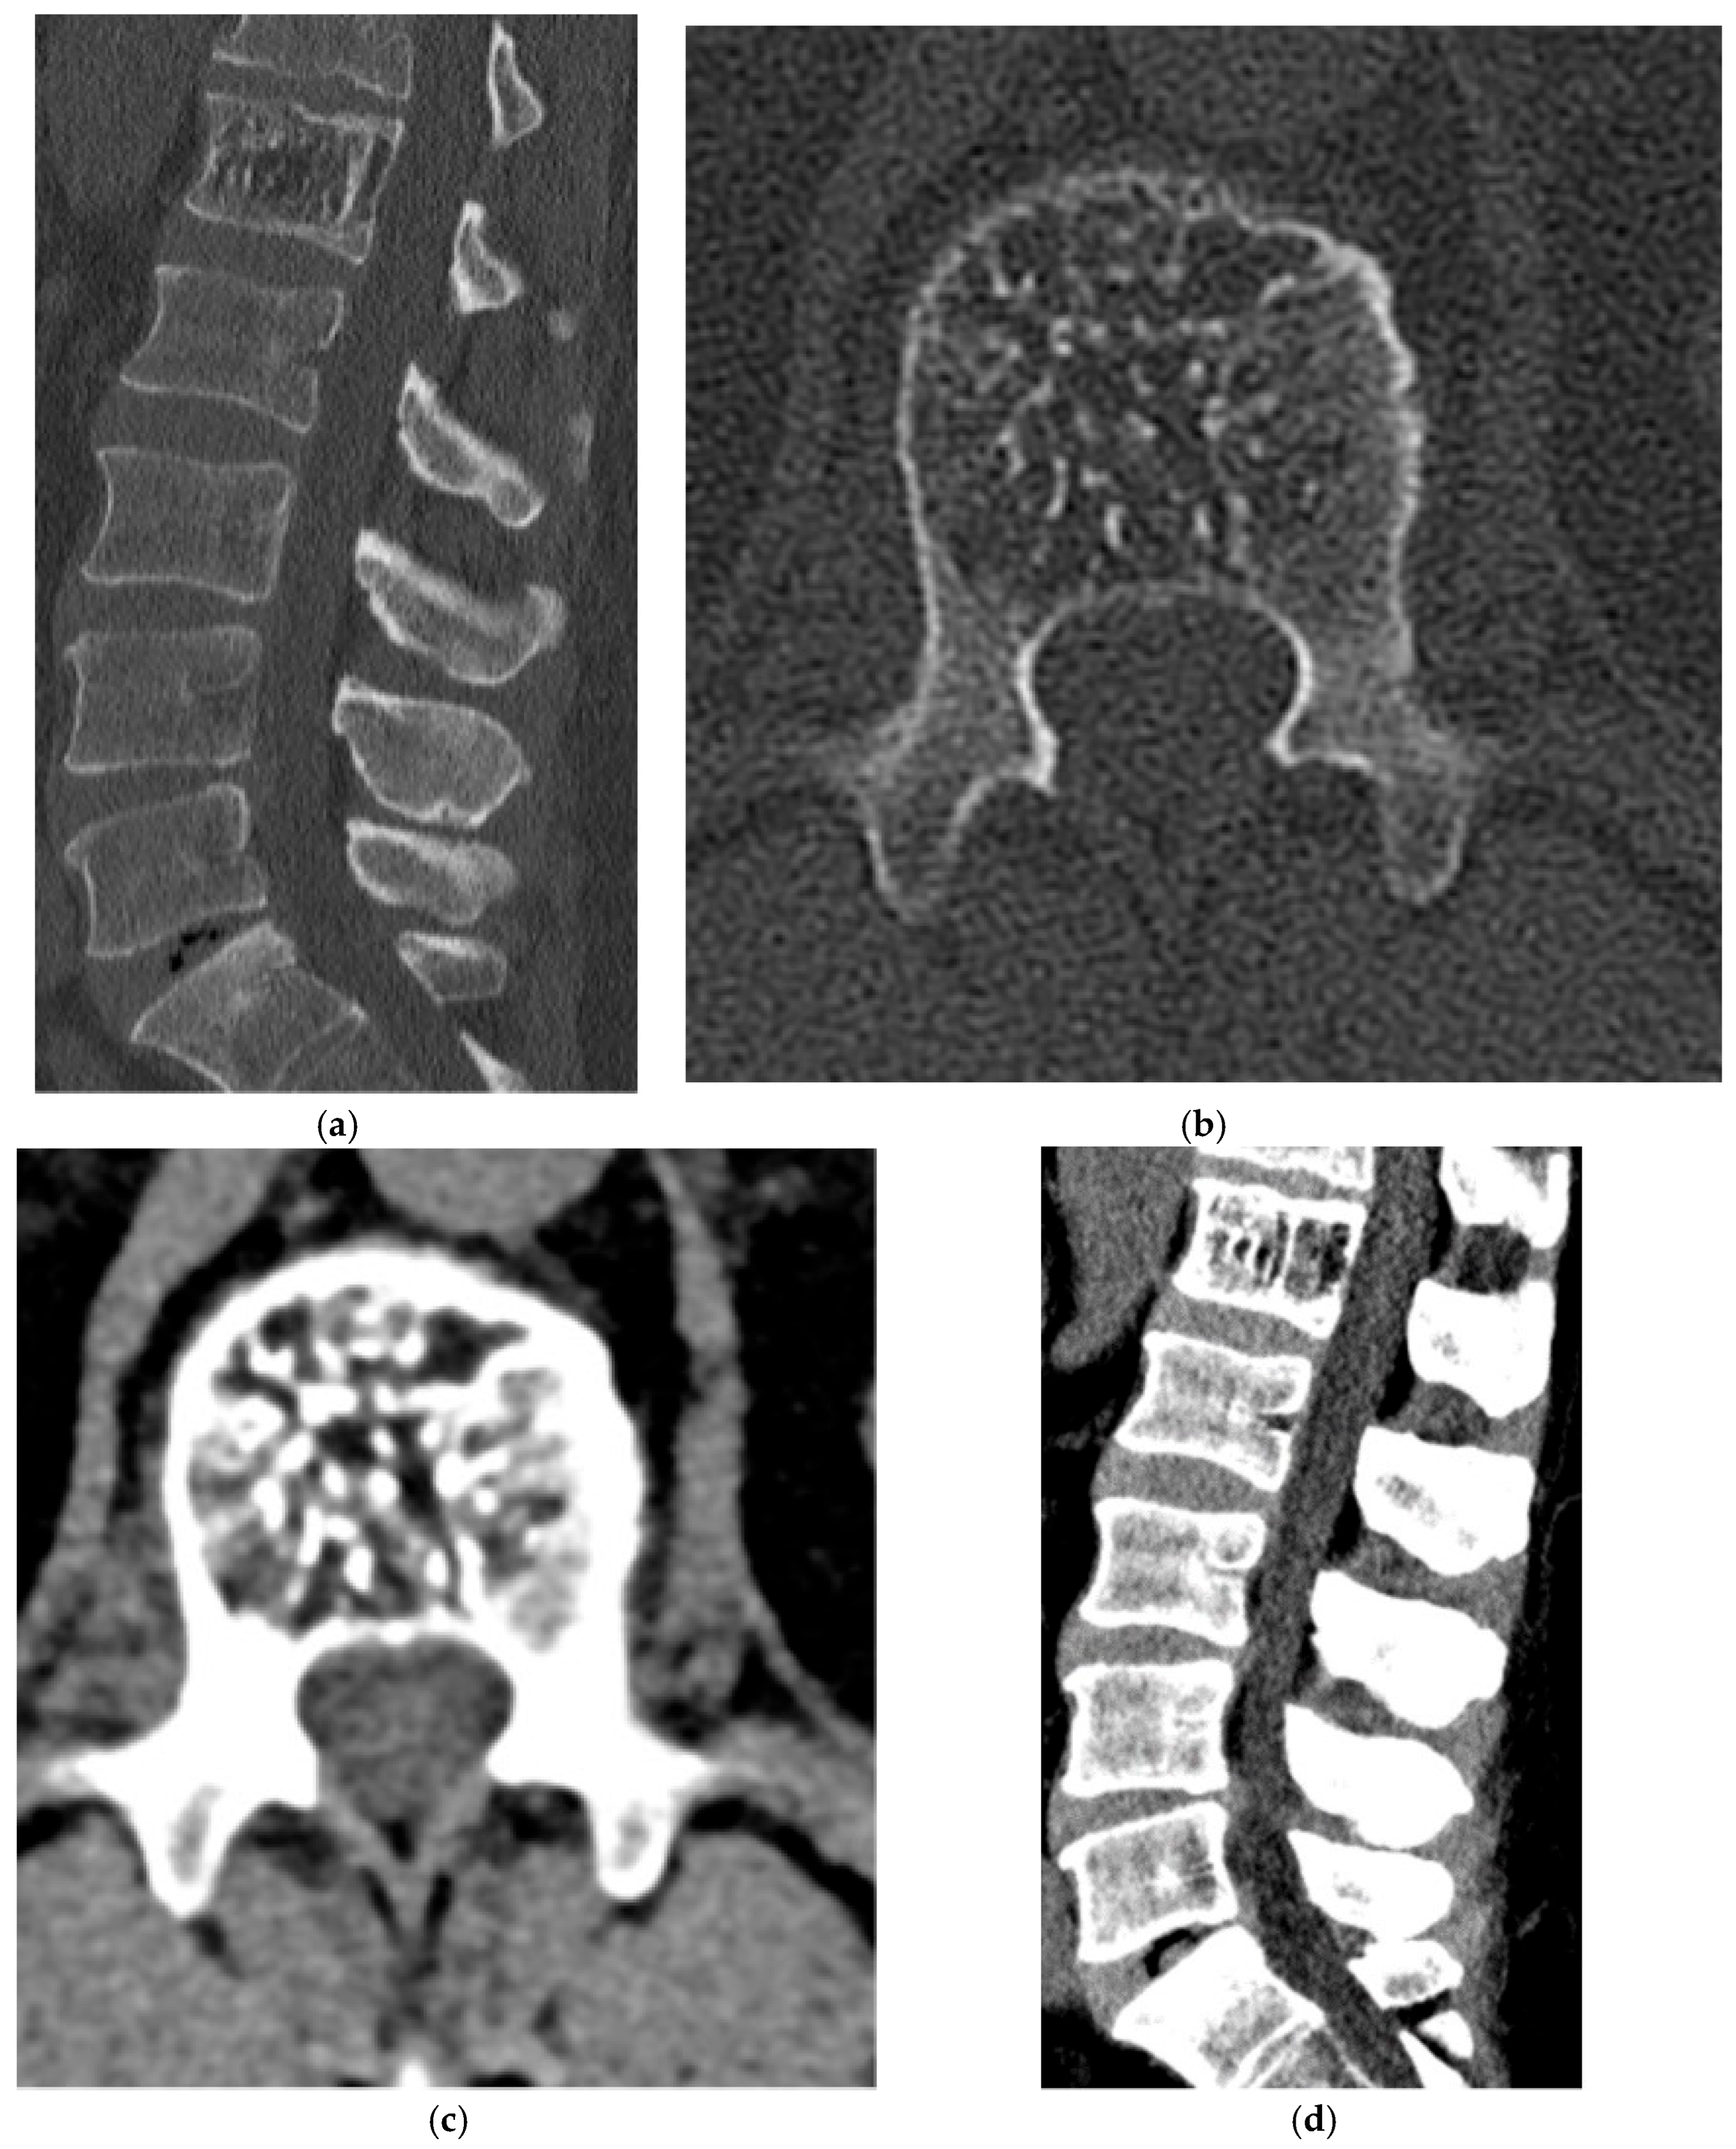

2.1.4. Osteosarcoma

2.1. Osteogenic